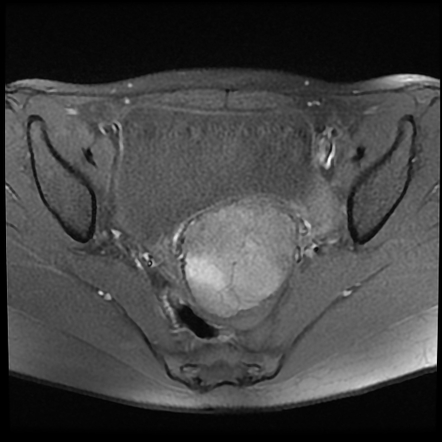

Myxoid Uterine Leiomyoma | Image | Radiopaedia.org

Webpathology.com: A Collection Of Surgical Pathology Images

Myxoid Uterine Leiomyoma | Image | Radiopaedia.org

Myxoid Uterine Leiomyoma | Radiology Case | Radiopaedia.org

radiopaedia.org

radiopaedia.org